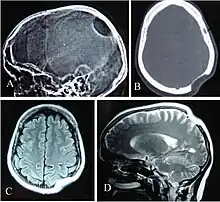

Often, Gorham's disease is not recognized until a fracture occurs, with subsequent improper bone healing. The diagnosis essentially is one of exclusion and must be based on combined clinical, radiological, and histopathological findings.[7] X-rays, CT scans, MRIs, ultrasounds, and nuclear medicine (bone scans) are all important tools in the diagnostic workup and surgical planning, but none has the ability alone to produce a definitive diagnosis. Surgical biopsy with histological identification of the vascular or lymphatic proliferation within a generous section of the affected bone is an essential component in the diagnostic process.[7][8][11]